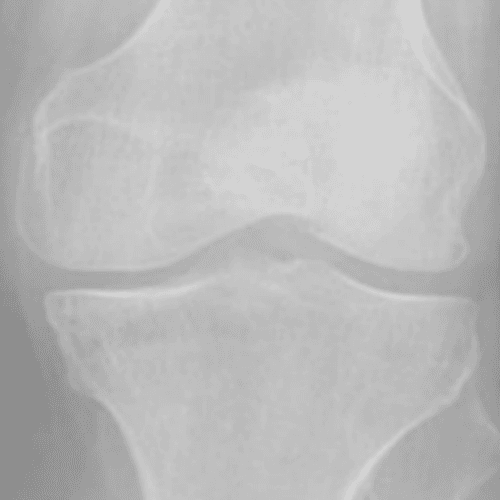

Kellgren and lawrence (KL) Grading System

통증이 발생한 무릎을 x-ray로 촬용한 관절염 결과를 총 4단계로 구분한 것을 KL Grading System 이라고 부르며

2~3단계의 환자들에게 무릎 연골 줄기세포 시술을 진행합니다.

Grade 0

정상 무릎